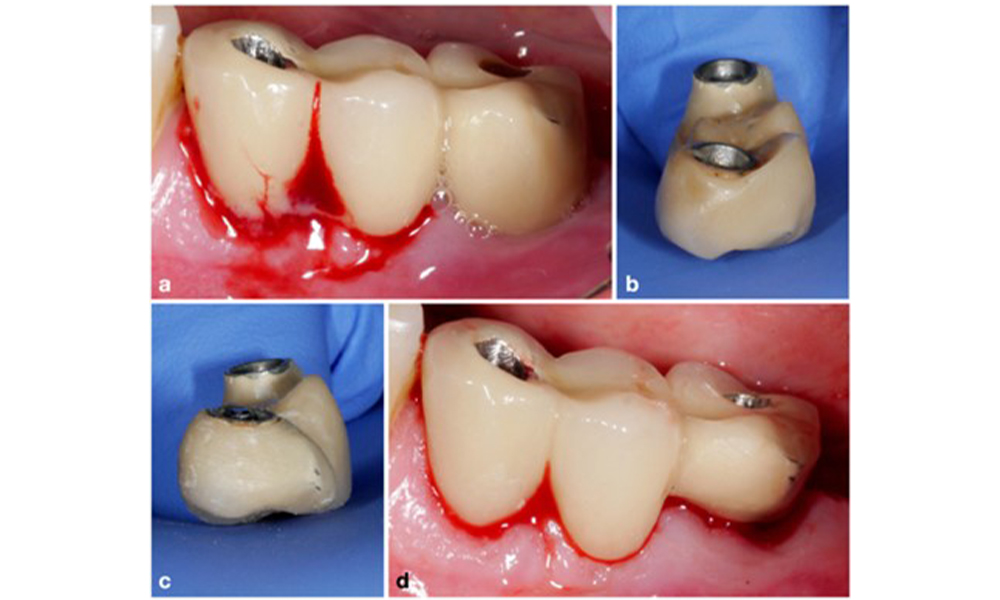

Протетичната реставрация трябва да бъде отстранена както по време на нехирургично, така и по време на хирургично лечение, за да се подобри достъпът до повърхността на импланта. Изборът на хирургична интервенция (напр. резективна, реконструктивна или комбинирана) зависи от няколко фактора: (1) морфология на дефекта (напр. хоризонтална, дехисценция, вътрекостна или комбинирана) (фигура 10), (2) повърхност на импланта ( т.е. обърната или модифицирана/"груба") и (3) наличие или липса на достатъчно кератинизирана и прикрепена лигавица.